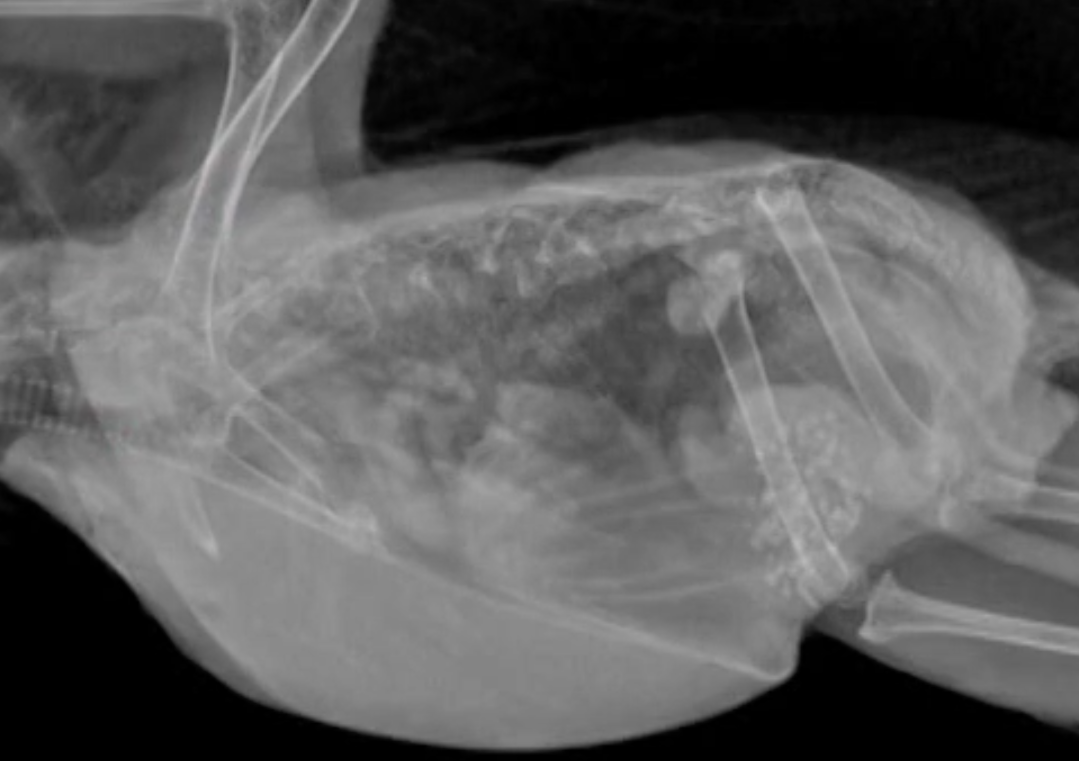

Vous êtes confus au sujet de votre radiographie aviaire? Cette session passera en revue l'anatomie radiographique et discutera de l'interprétation des images. Une série de cas sera utilisée pour démontrer différentes techniques et anomalies.

Aviaire / radiologie

Présenté par NatalieAntinoff DVM, DABVP (Avian)